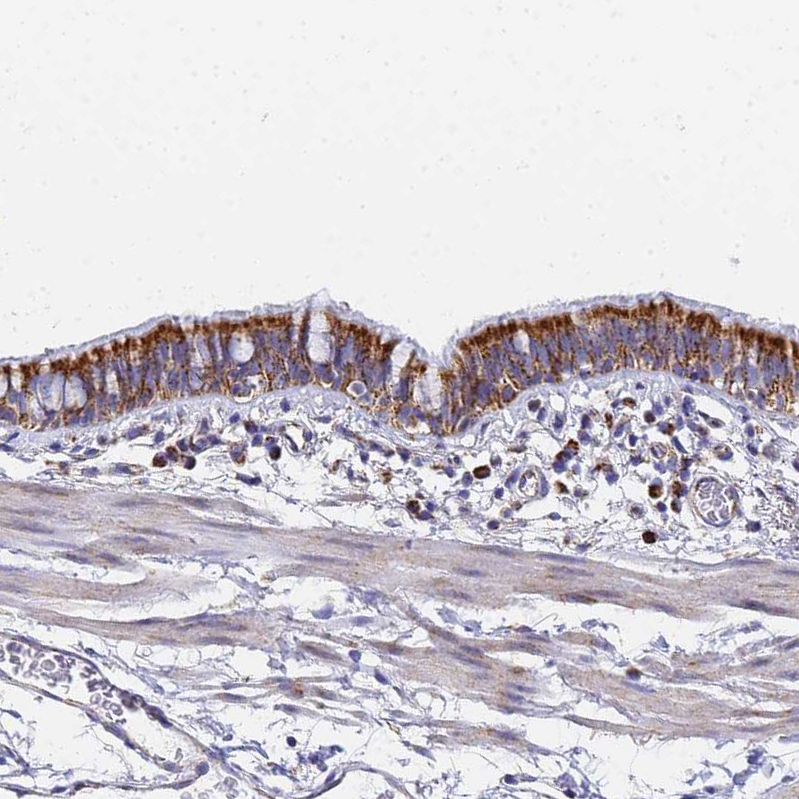

Immunohistochemical staining of human bronchus shows strong cytoplasmic granular positivity in respiratory epithelial cells.